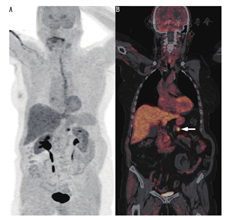

18F-FDOPA PET/CT显像对高分化GEP NETs及发生在前肠和后肠的NETs的灵敏度较低(25%)[43]。相反,18F-FDOPA PET/CT显像对低分化回肠NETs有很好的灵敏度(图4)。肿瘤生物合成5-羟色胺时芳香族氨基酸脱羧酶活性的增加是上述方法灵敏度高的主要原因。在这些情况下,18F-FDOPA PET/CT显像有助于肿瘤的定位和分期[44]。目前,尚不推荐在随访期间行18F-FDOPA PET/CT显像。

18F-FDOPA PET/CT显像检出低级别中肠NETs患者淋巴结、骨骼病变、肝转移要优于CT和111In-喷曲肽SSTR显像[44]。另一方面,对中肠NETs患者,18F-FDOPA PET/CT显像是否优于68Ga-DOTA-肽PET/CT显像尚不清楚,有必要进行大样本前瞻性研究[45]。毫无疑问,68Ga-DOTA-肽PET/CT显像在评估PRRT可行性的能力上优于18F-FDOPA。

相较于常规影像或SSTR显像,18F-FDOPA PET/CT显像似乎是检测回肠原发NETs的灵敏的功能影像工具(图4)[46]。由于手术切除与无症状生存、生活质量,甚至肿瘤转移性疾病等密切相关,尽管原发肿瘤的定位可能是一项挑战,但其对治疗计划仍至关重要[47]。首选显像剂的选择取决于临床评价、实验室评价和转移组织活检标本免疫组织化学标记的研究。